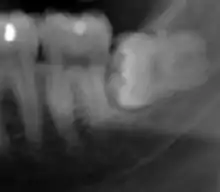

Las mandíbulas y los dientes humanos se han ido reduciendo proporcionalmente a la disminución del tamaño corporal en los últimos 30 000 años como consecuencia de las nuevas dietas y la tecnología. Hoy en día hay muchos individuos que no tienen espacio suficiente en la boca para sus terceros molares (o muelas del juicio) debido a la reducción del tamaño de las mandíbulas. En el siglo XX, la tendencia hacia dientes más pequeños pareció invertirse ligeramente debido a la introducción del flúor, que engrosa el esmalte dental, agrandando así los dientes.[70]